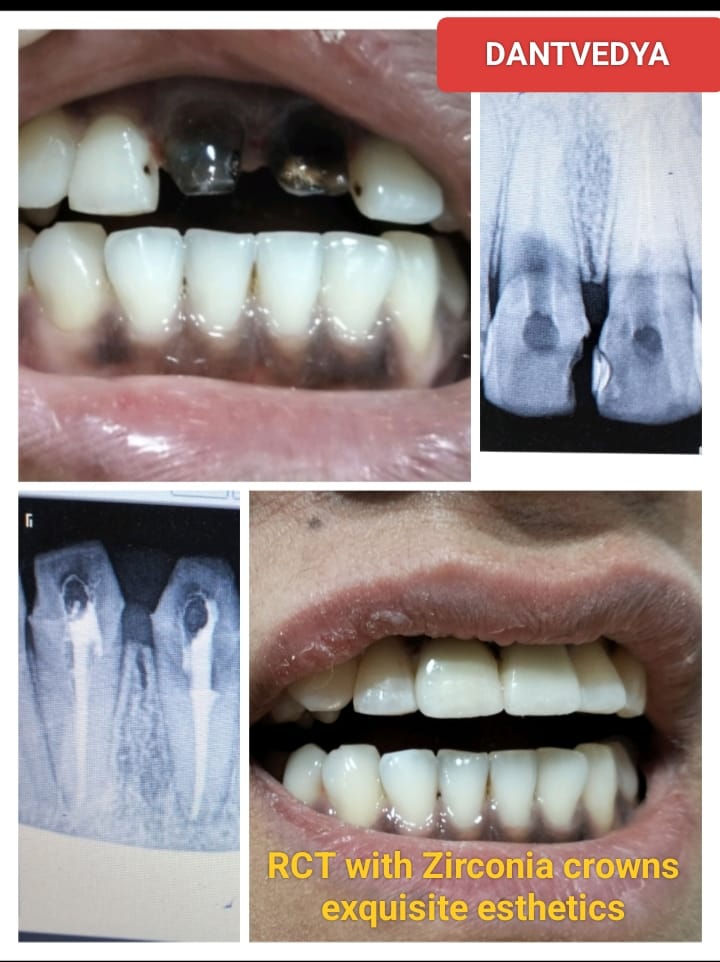

Root Canal Treatment

GALLERY